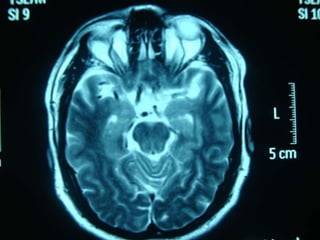

 ¿ La lesion cerebral es causada por una EVC

de tipo isquemico o hemorragico o por una

entidad no vascular?

 Respuesta: clinica y Tomografia

computarizada de craneo simple o RM craneal

simple

 ¿Cual es la localizacion y magnitud de la

lesion?

 Respuesta: TAC o RM

 Signo dela arteria cerebral media hiperdensa

 Atenuacion del nucleo lenticular

 Hipodensidad cortical o subcortical

 Edema cerebral

 Borrado de la region insular

 Borrado de surcos corticales

 Compresion ventricular

 Atenuacion de contraste cortico-medular